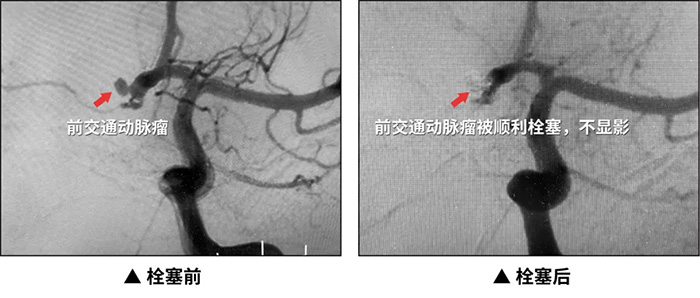

近日,上海藍十字腦科醫(yī)院神經(jīng)外科、腦血管病科、麻醉科團隊及導管室介入團隊密切配合順利搶救了一位酒后動脈瘤破裂危在旦夕的患者,并成功行動脈瘤栓塞治療,患者最終脫離危險,轉(zhuǎn)危為安。

方女士被第一時間轉(zhuǎn)入介入診療中心。造影明確患者左側(cè)頸內(nèi)動脈后交通動脈開口處可見一動脈瘤。為防止動脈瘤二次出血危及生命,決定給予其動脈瘤彈簧圈栓塞術(shù)。

經(jīng)兩小時的精細操作,動脈瘤被成功填塞。造影發(fā)現(xiàn)載瘤動脈通暢,動脈瘤不顯影,手術(shù)成功。方女士最終轉(zhuǎn)危為安。